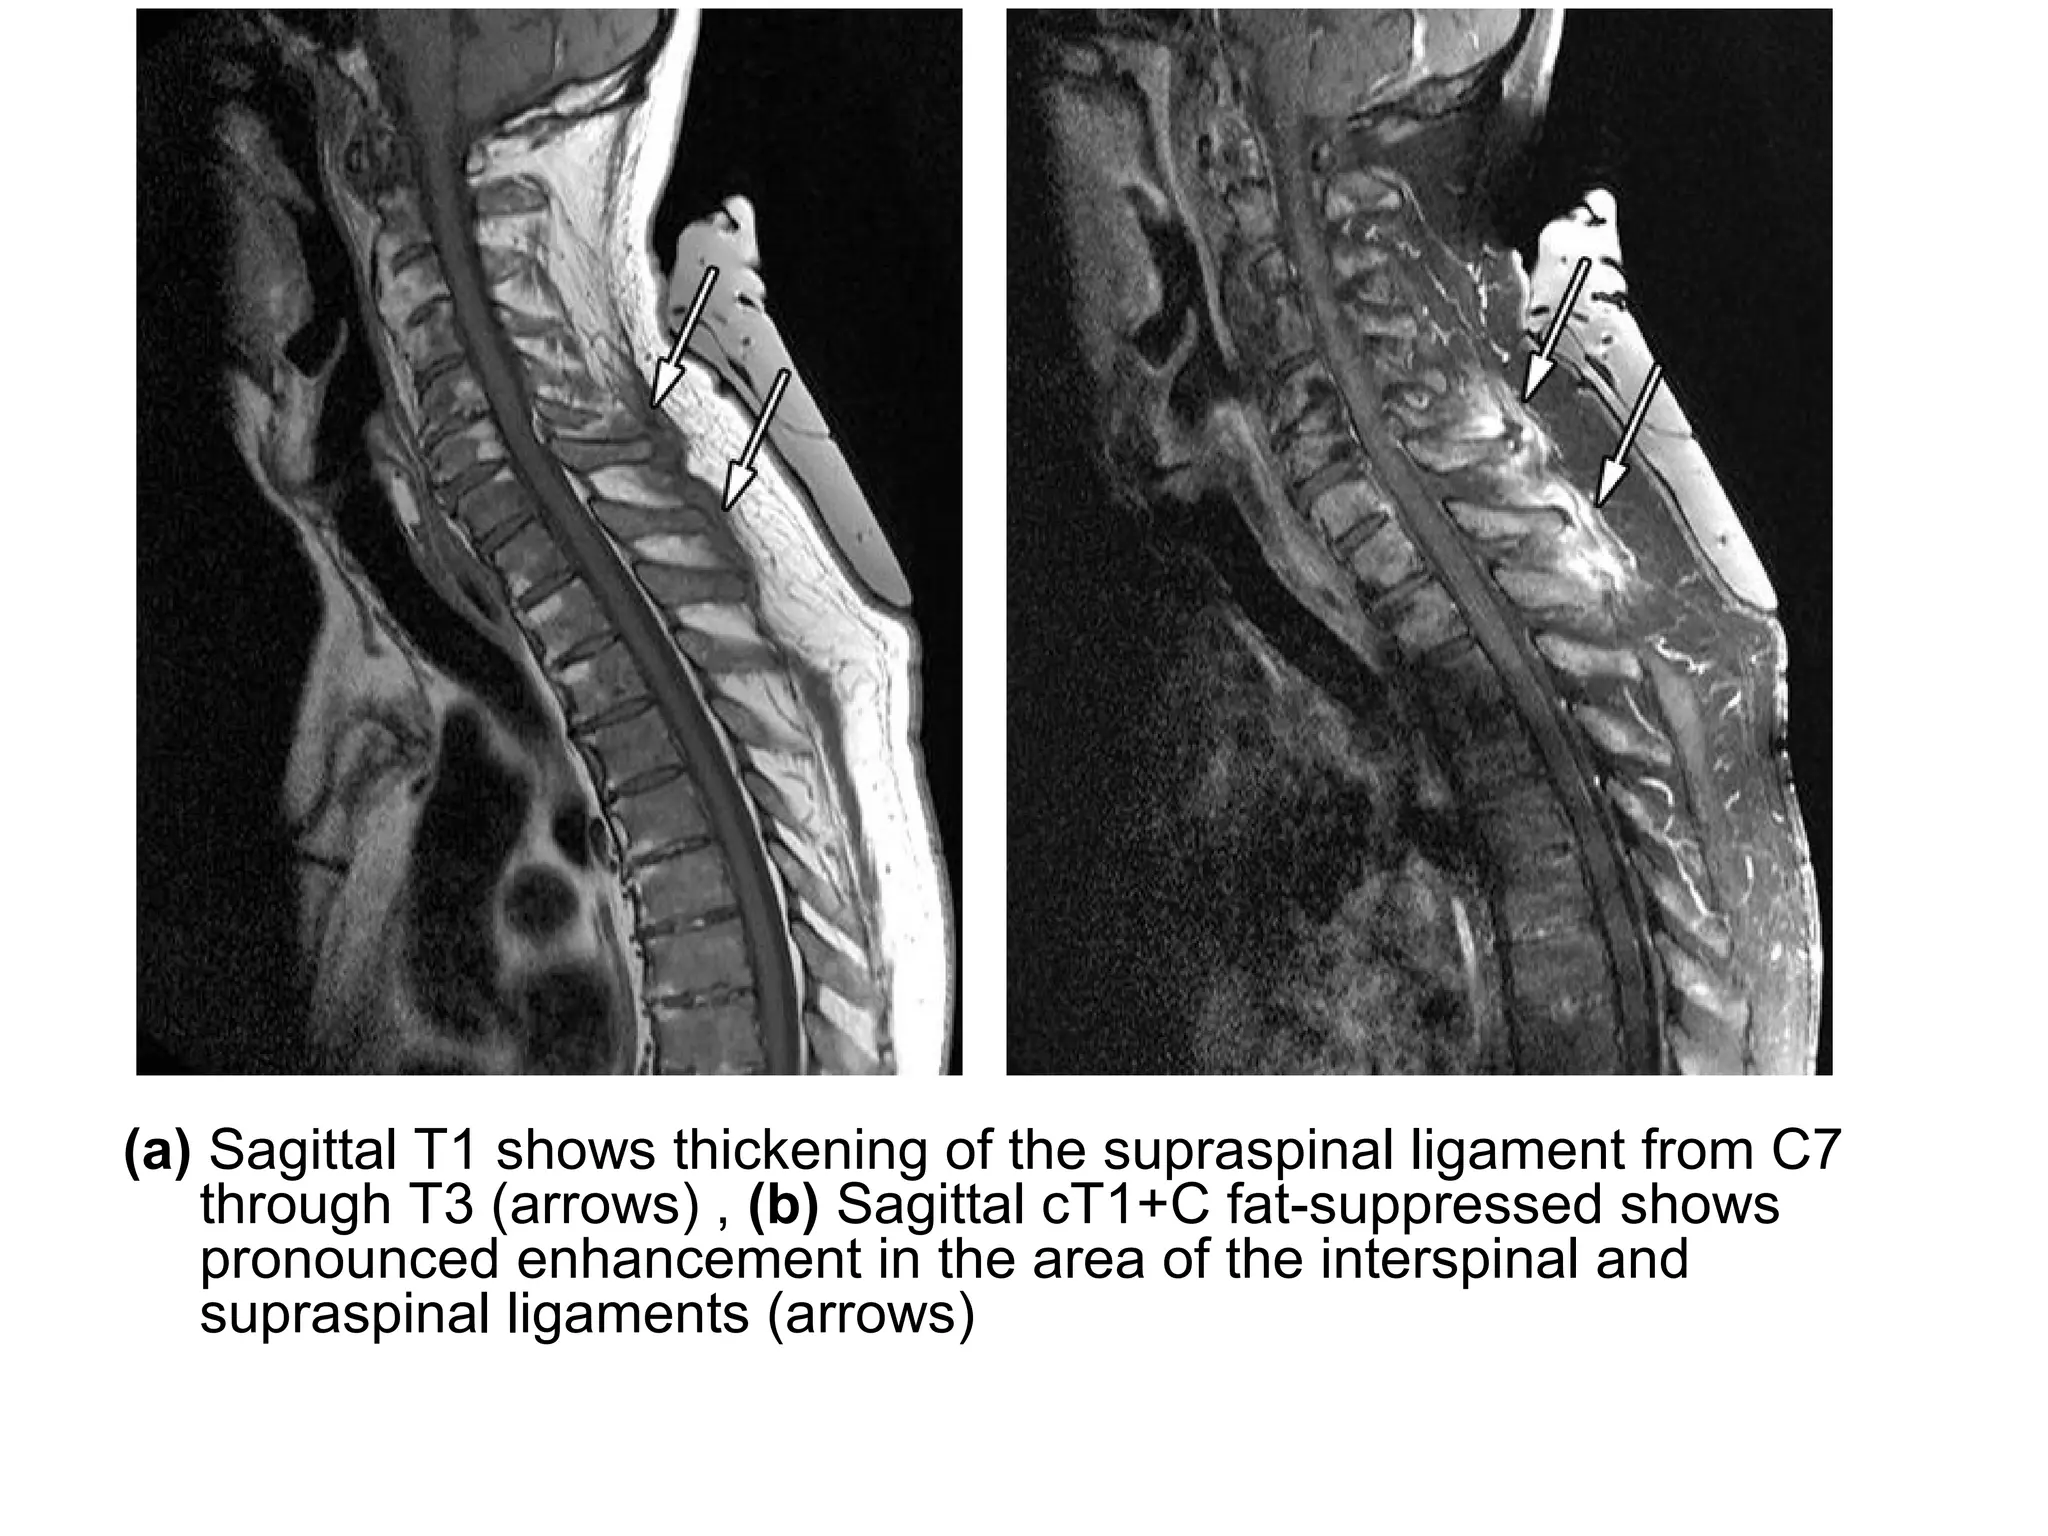

(a) Sagittal T1 shows thickening of the supraspinal ligament from C7

through T3 (arrows) , (b) Sagittal cT1+C fat-suppressed shows

pronounced enhancement in the area of the interspinal and

supraspinal ligaments (arrows)